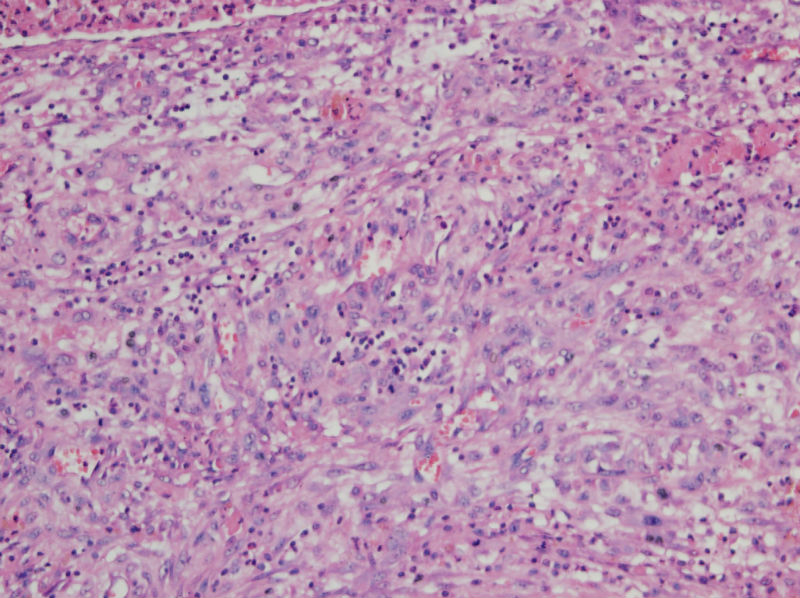

• 甲状腺囊肿,请老师们指教图3

图3

结节性甲状腺肿伴出血、囊性变。囊肿边上的滤泡大小不一,纤维组织增生,还可见炎细胞浸润。